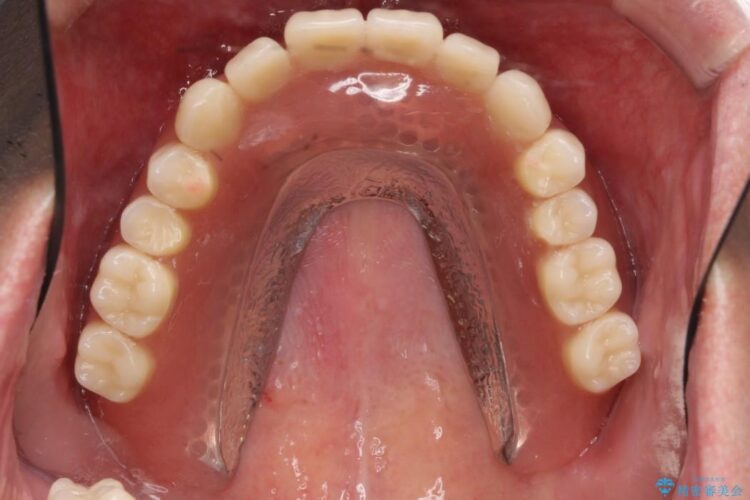

検査をしたところ、重度の歯周病を認めました。

状態から残せないと判断した歯を抜歯、噛み合わせ回復のため土台にインプラントを用いた上顎義歯にて補綴治療をすることとしました。

本症例では失った歯を補うため、マグネットを使用したインプラントの入れ歯(マグネットオーバーデンチャー)という維持機構を使用しました。